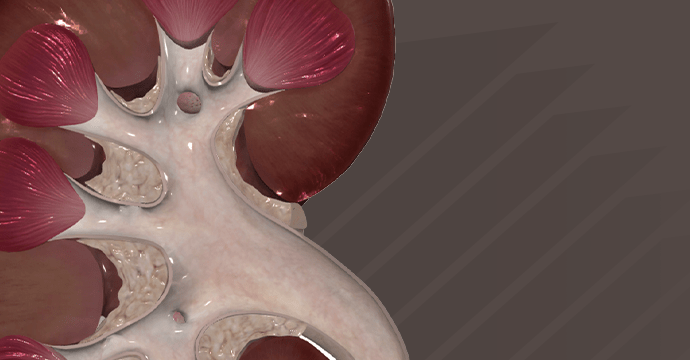

Take your understanding of human anatomy to the next level. Our comprehensive resources combine detailed information and stunning illustrations!

Enhance your studies for a truly dynamic learning experience. Explore interactive anatomy models from Complete Anatomy. Start mastering anatomy today with our free anatomy flashcards designed for quick review on the go.